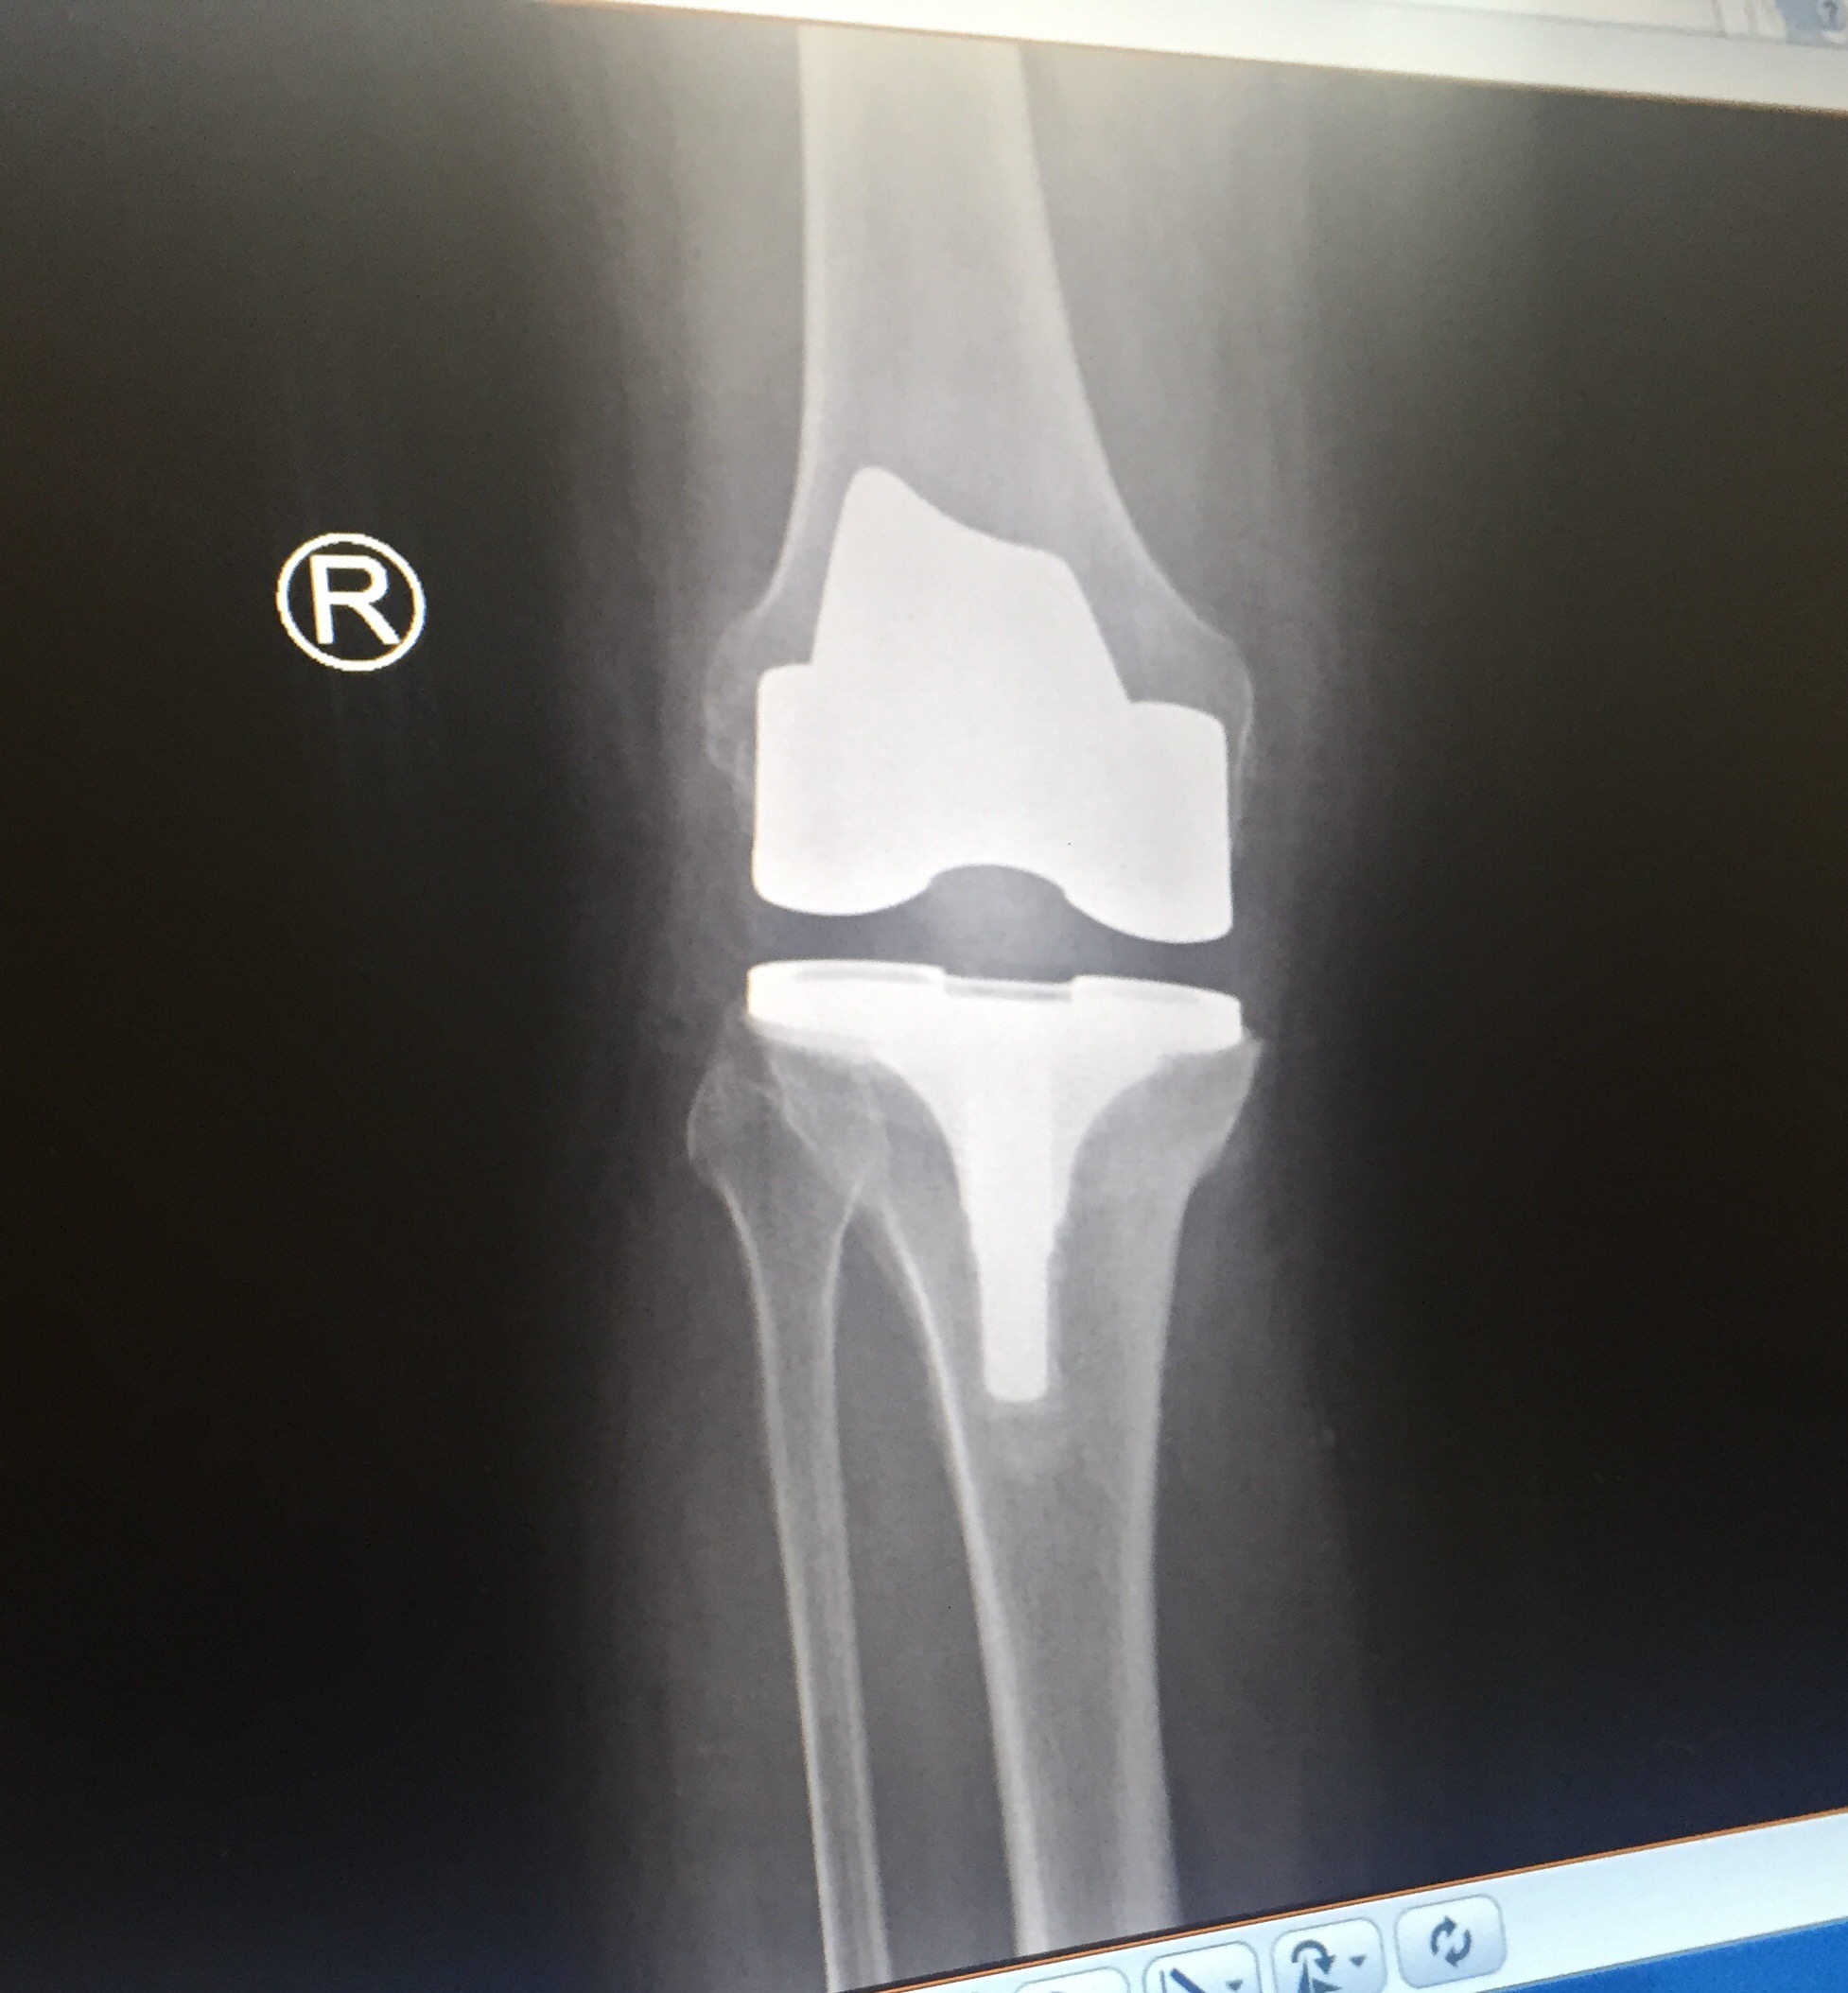

Graeme, my physio went onto his computer and showed me the results from the MRI I had at Flinders, and the Pet scan I had at the Royal Adelaide Hospital.

He read me the notes that were attached to each photo from the MRI and the Pet Scan, and I was able to photograph the MRI and the Pet Scan from the screen onto my iPhone.

This of course means that it is entirely possible that if I should need to have (as I do) another knee replacement, then the same thing could happen again, and I could have another stroke as a result of another knee replacement operation.

My left knee, the un-operated on knee, has rapidly become my “bad” knee, and so, unfortunately, such an operation is definitely “on the cards.”